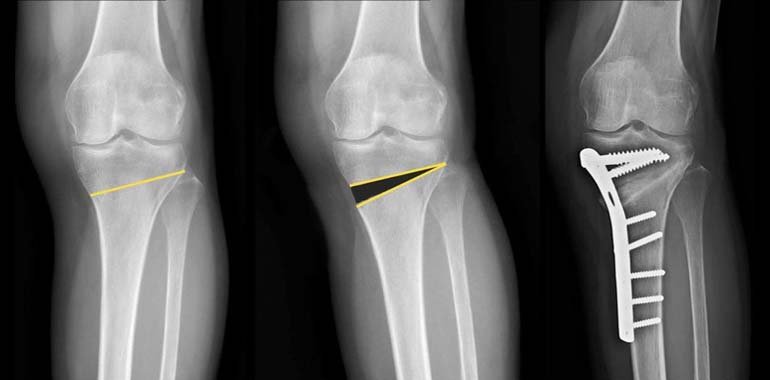

Corrective osteotomies : HTO, TCVO